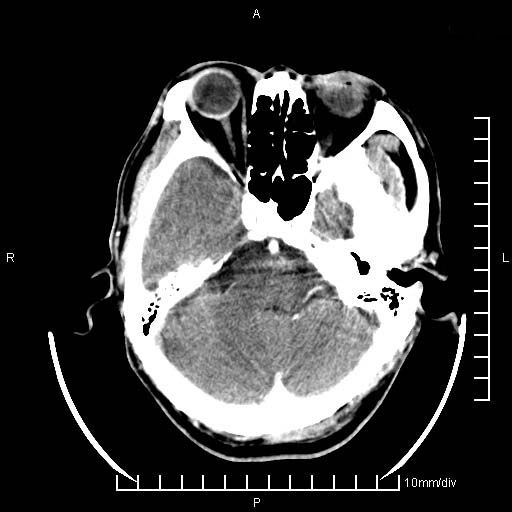

临床以双下肢浮肿,疼痛收治,无明显神经系统症状,既往无梗塞,出血病史。左颞叶见低密度灶,考虑什么?

考虑左侧颞叶脑软化灶。

无强化 无占位 软化灶吧

无强化、 无占位、局部脑沟增宽, 软化灶吧。